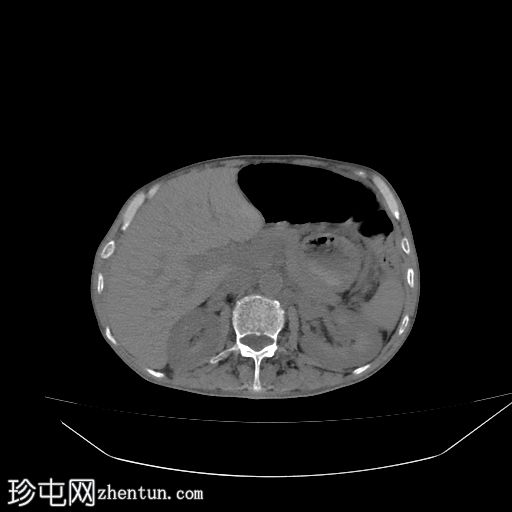

轴位

平扫